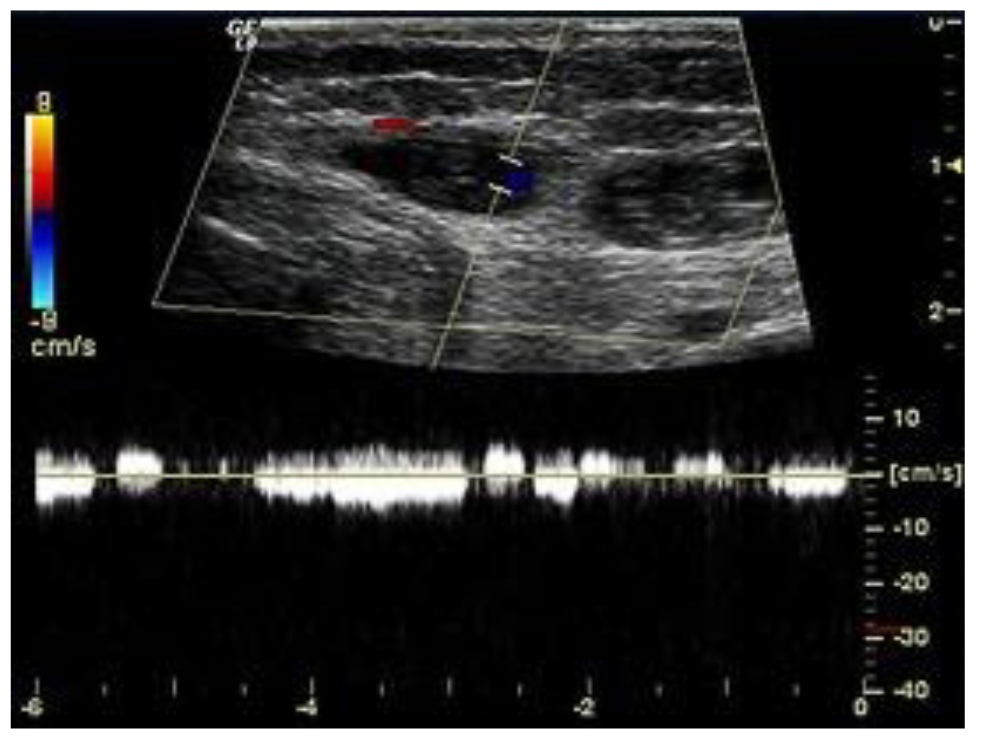

A program of complex preoperative examination included duplex scanning (DS) of vessels, ultraviolet scanning of soft tissues, and computed or magnetic resonance tomography (Figure 1). With these methods, the location and depth of the lesions and involvement of internal organs and adjacent anatomic structures were clarified.

Fig. 1. Duplex scanning of angiomatous tissues. Venous caverns with low-velocity blood flow based on the Doppler curve data

The study included patients with venous-cavernous forms of angiomatosis characterized by the existence of caverns, grapelike venous cavities separated with thin-walled trabeculas. According to their size, caverns were classified to small (5-20 mm), medium (21-30 mm), and large (>30 mm). The size of venous caverns in the analyzed clinical cases ranged from 5 to 32 mm, and the depth of the lesions ranged from 7 to 25 mm. Flebolytes were identified in 9 (45.2%) patients.